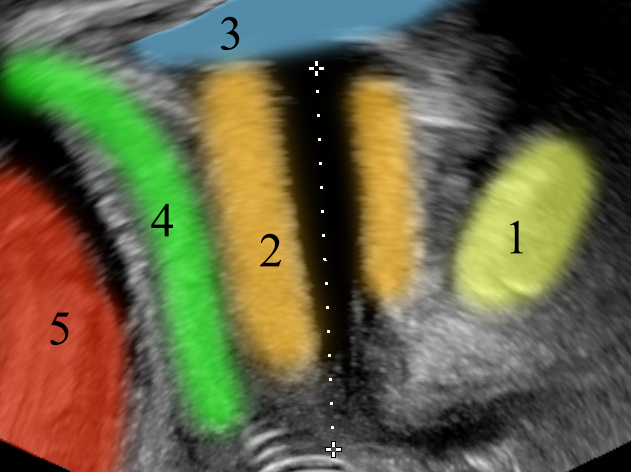

Normal urethra anatomy. 1: symphysis pubis, 2: urethral sphincter, 3: bladder, 4: vagina, 5: rectum.